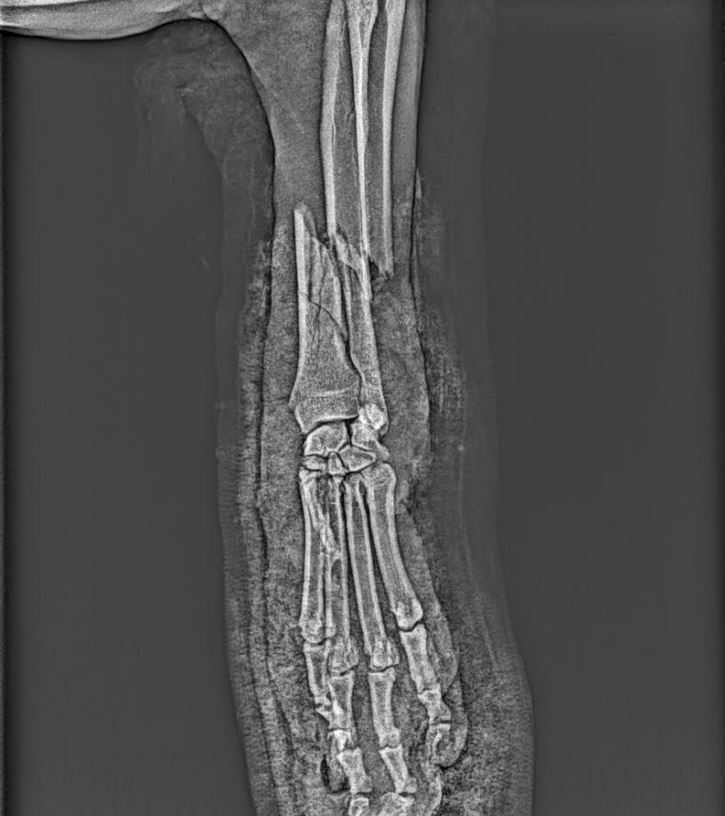

Veronika: ,, S panem Padevětem jsem se seznámila včera za hodně smutných okolností. Cestou pro malou do školky jsem ho našla klečet zoufalého u silnice nad jeho psem Blackem. Stala se úplně pitomá schoda okolností. Pán šel venčit Blacka k rybníčku a cestou mu házel míček. Blackovi se ale jednou nepodařilo míč chytit a odrazil si ho čumákem přímo do silnice, kde za normálních okolností jezdí tak desetina aut, ale jelikož tudy teď vede objížďka.....zkrátka Black naběhl přímo pod kolo autobusu, který mu doslova sešrotoval přední nohu. Jeden další kolemjedoucí pán nám pomohl pejska odnést ke mě do auta (díky neznámý pane:-)...)a odvezla jsem Blacka i s páníčkem na Veterinární kliniku. Než jsme tam dojeli pes upadl do šoku, což je akutní život ohrožující stav a bylo potřeba ho stabilizovat. Bude žít, ale musí podstoupit poměrně náročnou operaci nohy. Kostní operace u psů jsou finančně hodně nákladná záležitost a to je vlastně důvod proč to tu celé píšu. Napadlo mě že každý v domácnosti čas od času používáme med. Kupte si med od pana Padevěta, pomůžete mu tím zaplatit náročnou operaci pro jeho psa. Díky..."